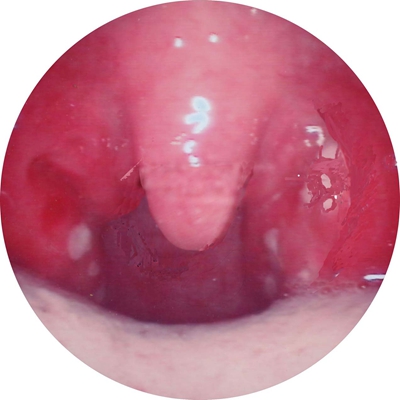

扁桃體惡性腫瘤圖片

扁桃體癌圖 (9)